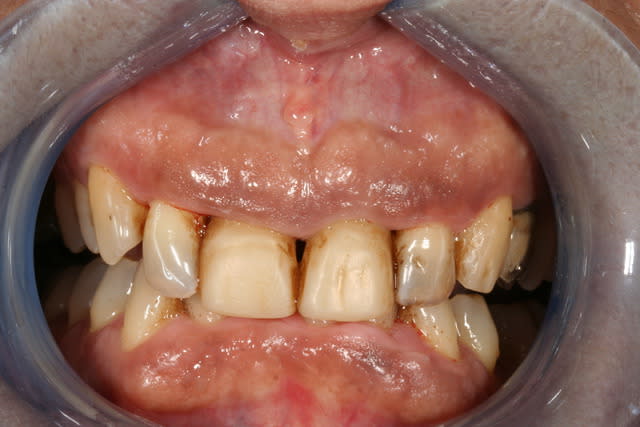

cette patiente que je suis en controle depuis 2 ans, se décide à faire quelque chose pour son sourire.

grosso modo depuis 2 ans, pas de soucis particuliers, pas de caries, faut faire un peu gaffe à la paro mais elle est plutôt motivée et ça se passe bien.

elle a plein de vieux compos d'une mauvaise couleur, au joints colorés, des dents de couleur pas vraiment toutes pareilles ; et un sourire très gingival.

je ne sais pas trop d'ou ça viens, de mylolyses traitées au compo ou d'un épisode de caries au collet ?

elle ne fume pas, bois du thé, un peu de café.